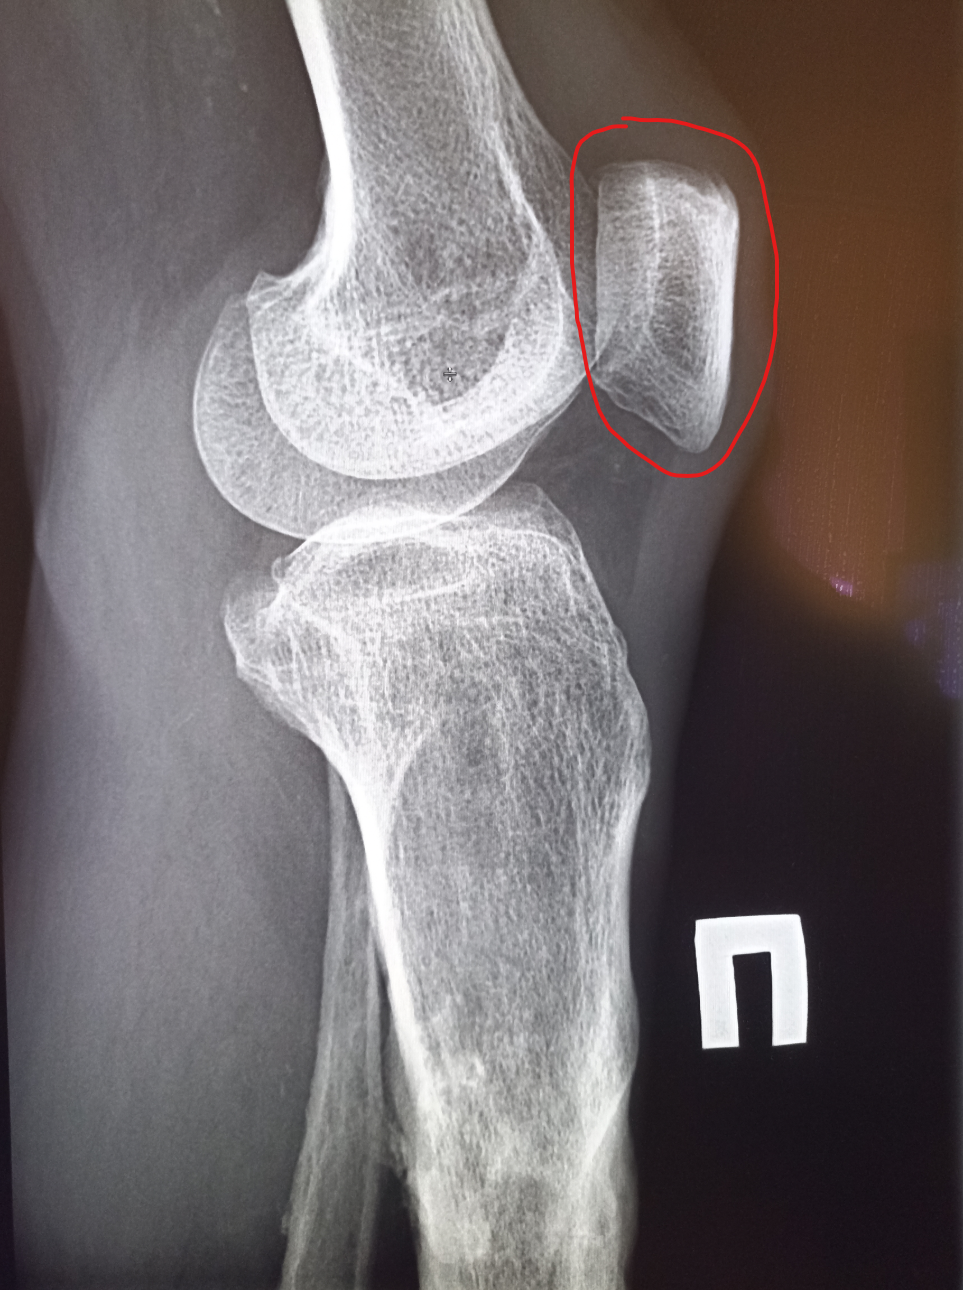

Здравствуй двачик, пишет вам простой рентгенолог из мухосранской поликлиники, сегодня я буду флексить зарплатой за ноябрь! Аж ПЯТЬДЕСЯТ ТРИ ТЫЩИ ПЕРЕВЕДУТ! С пруфом! А чего достигли вы? Ну и в доктора тож поиграем! Я буду вам картинки показывать, а вы пиздецомы находить! Найдите пиздецому на фтчк! Отчет еще по фог считать квартальный и годовой сегодня :-(